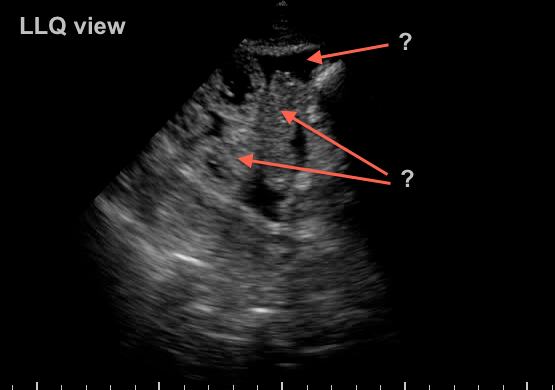

73 yr old woman recovering from septic shock with abdominal distension and difficulty tolerating enteral feeds…

what do you see?

Extensive third spacing from resuscitation has resulted in bowel edema and ascites.  Another “benign” effect of massive crystalloid use… A bedside 22g US guided tap confirms benign transudate.